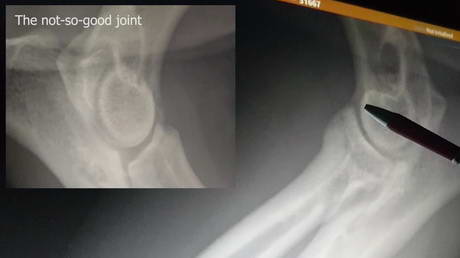

Elbow Dysplasia

Play this video

01 Oct 2017

(Duration 01:40)